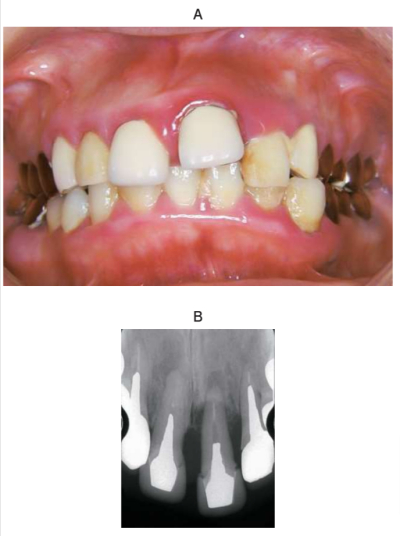

40 歳の女性。嚙み合わせると上顎左側中切歯が動くことを主訴として来院した。1年前から食事中に違和感があったがそのままにしていたという。検査の結果、慢性歯周炎と診断した。初診時の口腔内写真とエックス線画像を別に示す。歯周組織検査結果の一部を表に示す。

⎿1 の病態の主な修飾因子はどれか。2つ選べ。